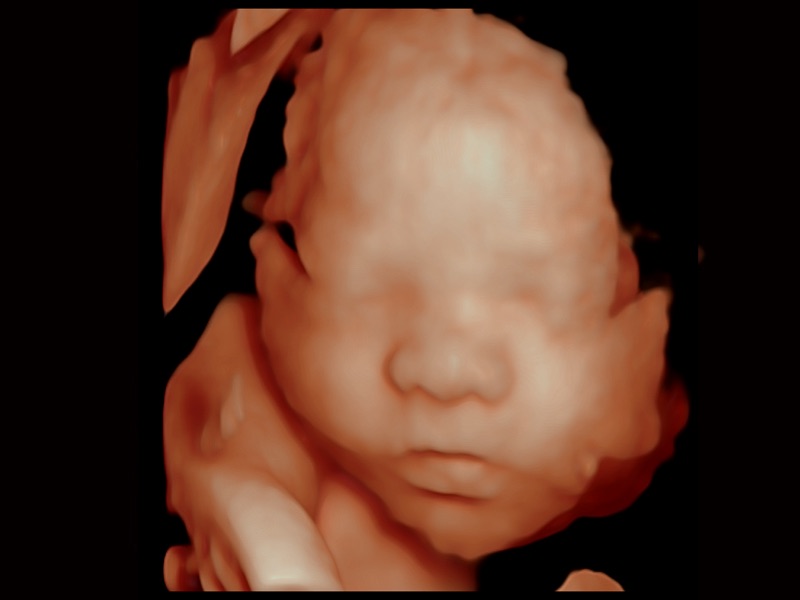

三维光影成像技术采用新型的渲染方式,增强边缘信息,使得轮显示清晰完整,为临床提供丰富、直观的三维结构,提供临床诊断准确性。